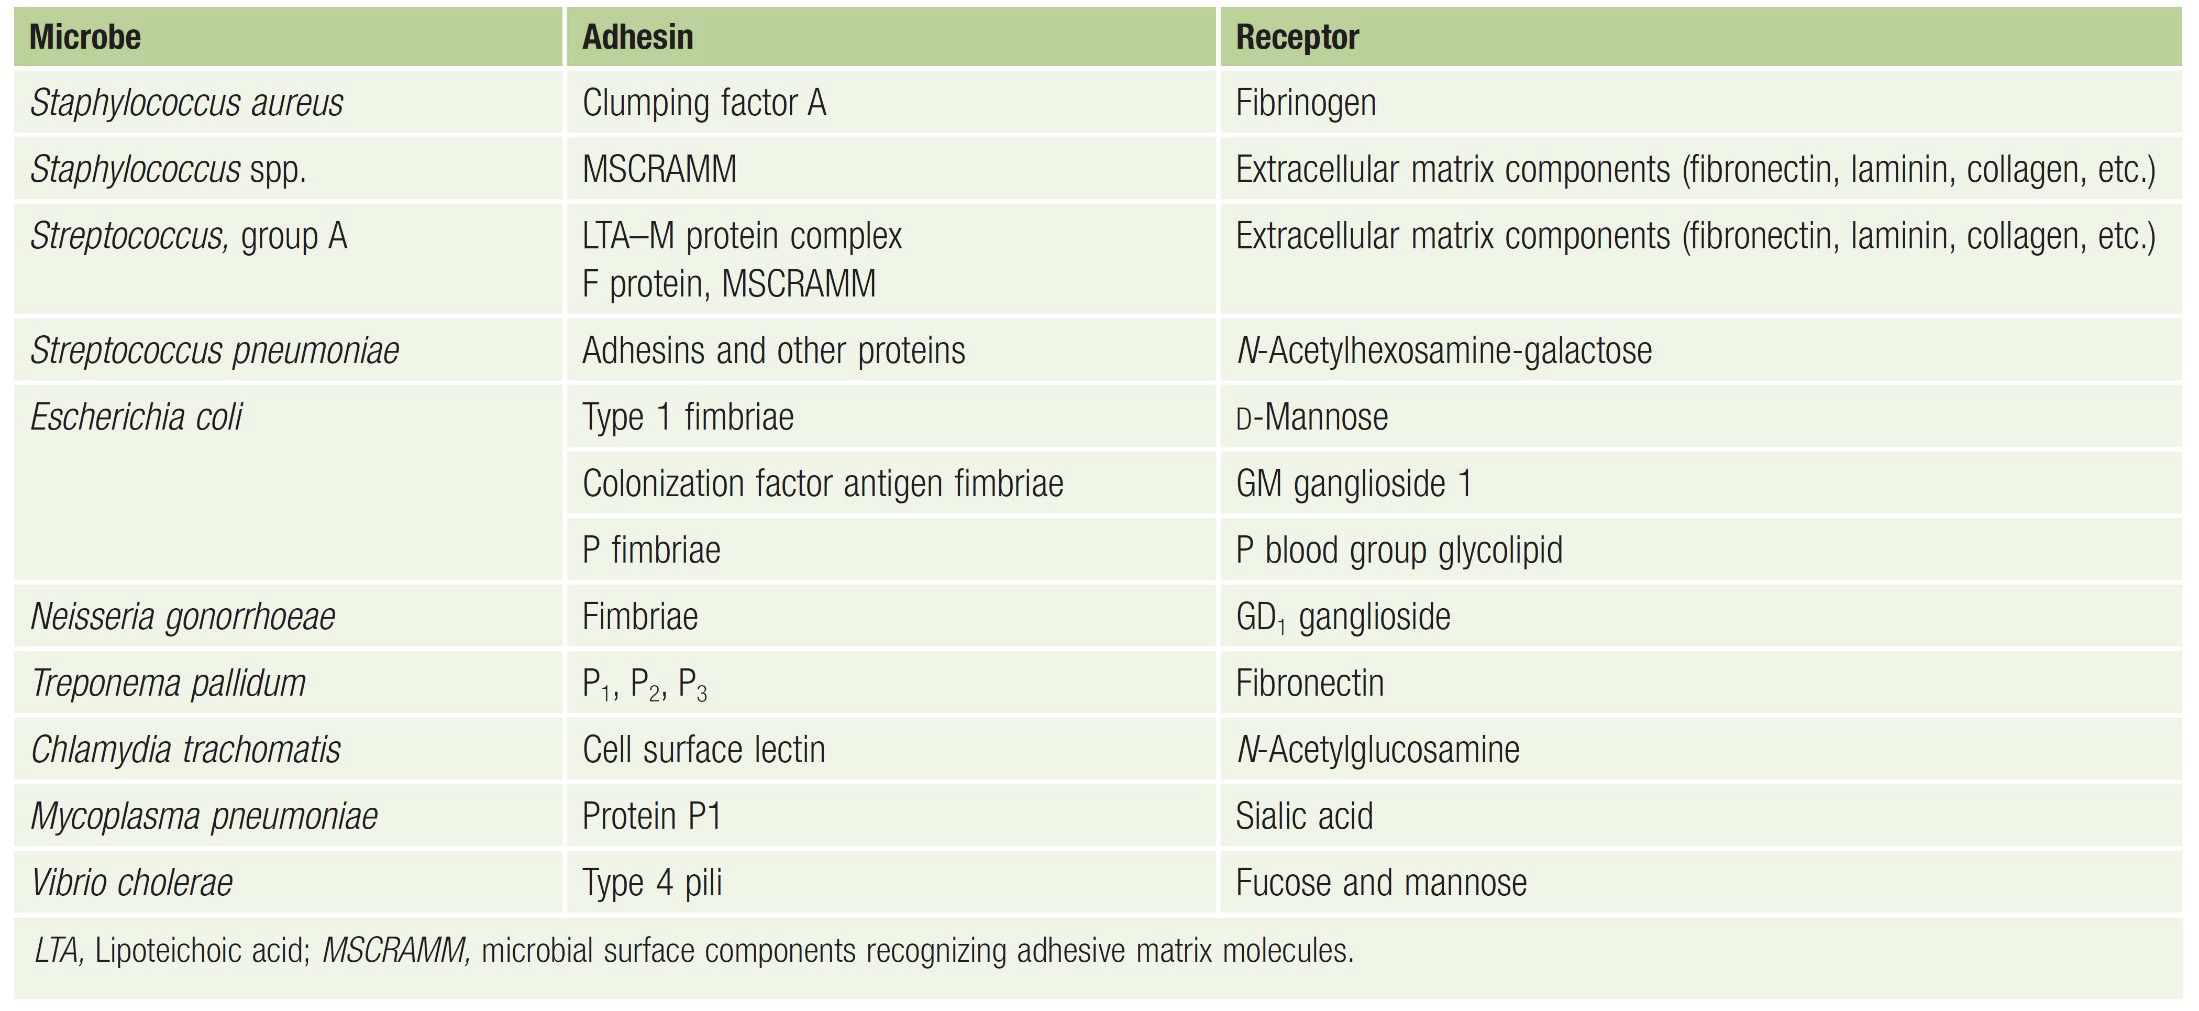

致病

黏細胞

gram’s negative: Pili, Fimbriae

Endotoxin

A.K.A Lipopolysaccharide (LPS)

- 可活化血小板及凝血系統為革蘭氏陰性菌造成敗血症的主因

- T independent

A-B exotoxin

- B for bounding, A for action

都要背。。。